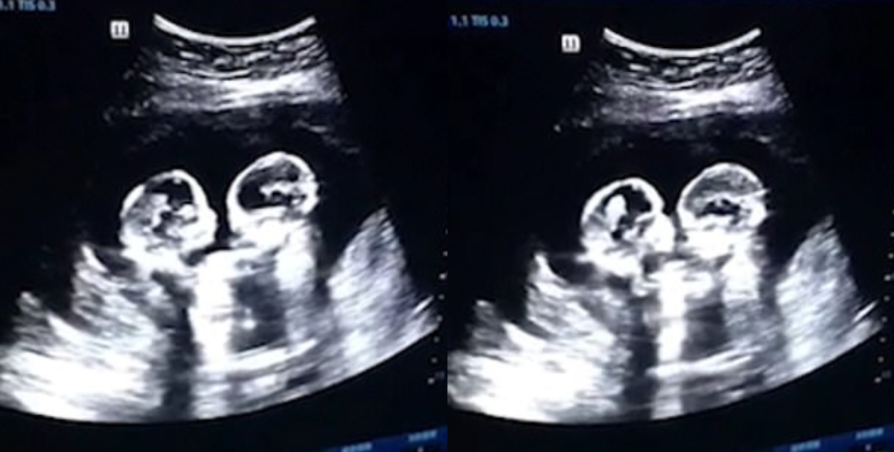

ജനിക്കും മുൻപുതന്നെ  ഇൻറർനെറ്റിൽ ഇടം നേടിയ   ചൈനീസ് ഇരട്ട കുട്ടികളാണ് ചെറിയും, സ്ട്രോബെറിയും.  സ്‌കാനിങ്ങിനിടെ അമ്മയുടെ വയറ്റിലിരുന്നും 'അടികൂടുന്ന' ഇരുവരുടേയും വീഡിയോ പുറത്തുവന്നതോടെയാണ് ജനിക്കും മുന്‍പേ ചെറിയും സ്‌ട്രോബറിയും വൈറലായത്.

ചൈനയിലെ ഷുവാനില്‍ നിന്നുള്ള ദമ്പതികളുടെ ഇരട്ട പെണ്‍കുട്ടികളാണ് ഇവര്‍. ഗര്‍ഭിണിയായിരിക്കെ ഡിസംബറില്‍ നടത്തിയ സ്‌കാനിങിനിടെയാണ്അമ്മയുടെ  വയറ്റിലിരുന്ന്  മുട്ടനാടിയുണ്ടാകുന്ന സമാനമായ കാഴ്ച ഡോക്ടറുടെ ശ്രദ്ധയില്‍പ്പെട്ടത്. ഈ കാഴ്ചയിൽ കൗതുകം തോന്നി കുട്ടികളുടെ പിതാവായ ടോ ആണ് വീഡിയോ പകര്‍ത്തി വീഡിയോ ആപ്ലിക്കേഷനായ ഡോയിനില്‍ അപ്ലോഡ് ചെയ്തത്.

'വയറ്റിലിരുന്നും അടി കൂടുന്ന കുഞ്ഞുങ്ങള്‍' എന്ന ക്യാപ്ഷനോടെയാണ് വീഡിയോ അപ്‌ലോഡ് ചെയ്തത്. വീഡിയോ പുറത്തു വിട്ടു നിമിഷങ്ങൾക്കുള്ളിൽ തന്നെ  നിരവധിപേരാണ് ഈ വീഡിയോ കണ്ടത്. സഹോദരിമാരുടെ ഈ തല്ലുകൂടൽ മണിക്കൂറുകള്‍ക്കുള്ളില്‍ യുട്യൂബിലെത്തുകയും ട്രെന്‍ഡിങ് ലിസ്റ്റില്‍ ഇടം നേടി വൈറലാവുകയും ചെയ്തു. കുട്ടികള്‍ ജനിച്ചതിനു ശേഷമായിരുന്നു വീഡിയോ പുറത്തുവിട്ടത്.

ആദ്യ സ്‌കാനിങില്‍ ഇരുവരും അടികൂടുകയാണെങ്കിലും പിന്നീടുള്ള സ്‌കാനിങില്‍ ഇരുവരും കെട്ടിപ്പിടിച്ചിരിക്കുന്നതും കണ്ടിട്ടുണ്ട്, കുട്ടികളുടെ ആരോഗ്യത്തെ കുറിച്ച് അല്‍പം ആശങ്കകളുണ്ടായിരുന്നുവെങ്കിലും നാല് മാസത്തിനു ശേഷം ഇരുവരേയും ശസ്ത്രക്രിയയിലൂടെ പുറത്തെടുത്തെന്നും ചൈനീസ് മാധ്യമത്തിന് നല്‍കിഅഭിമുഖത്തില്‍ ടോ പറഞ്ഞു.

മോ-മോ ട്വിന്‍സ് എന്നറിയപ്പെടുന്ന ഇരട്ടകളാണ് ചെറിയും സ്‌ട്രോബറിയും. സാധാരണയായി ഇരട്ടക്കുട്ടികള്‍ ഗര്‍ഭപാത്രത്തിലെ രണ്ട് അറകളിലായാണ് വളരുന്നത്. എന്നാല്‍ ഇവര്‍ ഒരേ അറകളിലാണ് ഉണ്ടായിരുന്നത്. ഇത്തരം ഇരട്ടങ്കൽ ഉള്ള  ഘട്ടങ്ങളിൽ പ്രസവം  ബുദ്ധിമുട്ടവനാണ് സാധ്യതയുണ്ടാകാറ്, ന്‍സ് യുകെയുടെ റിപ്പോര്‍ട്ട് പ്രകാരം 60,000ല്‍ 1 എന്ന നിലയിലാണ് ഇത്തരം കുട്ടികള്‍ ജീവനോടെ തുടരാനുള്ള സാധ്യത. എന്നാല്‍ ചെറിയും സ്‌ട്രോബറിയും  കുഴപ്പങ്ങളൊന്നും  കൂടാതെ ശസ്ത്രക്രിയയിലൂടെ പിറന്നുവീണു.2019 ഏപ്രില്‍ രണ്ടാമത്തെ ആഴ്ചയിലായിരുന്നു ഇരുവരുടേയും ജനനം.